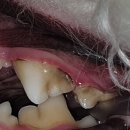

• ABC 동물의료센터 | 안양, 과천 24시 동물병원 abc동물의료센터 솔직후기!!

입니다. pf.kakao.com 카카오 채널 링크도 올려드려요!! 문의사항이나, 아이 관련 사진 등등 전부 여기로 보내주셔서 너무 편리하고 좋았습니다! ㅎㅎㅎ ABC 동물의료센터 경기도 과천시 별양상가3로 14 112,113,114호 ​ #안양동물병원 #과천동물병원 #과천ABC동물병원 #과천24시동물병원 #인덕원24시동물병원 #과천야간...

오롯이 내공간(2025-05-16 07:50:00)